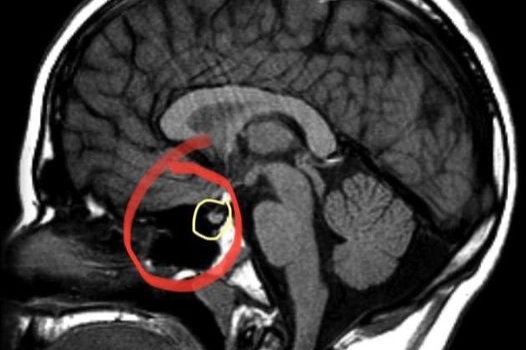

On top of the medical expenses that come with fertility treatment, both Kacey and Jerrod were diagnosed with COVID-19 last year, which put them both out of work for a few weeks. Then just last week, Kacey was rushed to the emergency room when her vision doubled and she had an intense migraine. She got an MRI which revealed that her tumor is currently the largest it's ever been (circled in yellow is a normal sized gland, Kacey's has currently swelled to the size of the red circle).